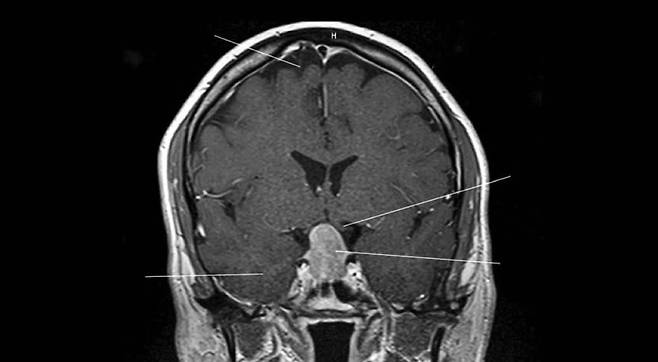

치료법은 고사하고 진단조차 자기공명영상과 컴퓨터 단층 촬영 스캔뿐. 훨씬 뒤에 아밀로이드와 타우 단백질의 수치를 측정할 수 있는 뇌척수액 검사가 개발됐다.

그는 자신의 알츠하이머 유전자를 발견하기 위해 사서 출신인 아내와 탐정처럼 가족 계보도를 추적해서 대가족의 이야기를 완성하고, 아밀로이드와 타우로 위축된 자신의 뇌 사진을 보면서 ‘나 홀로 시사회’를 즐기고, 신약을 위한 임상 실험 참가자가 되어 언어를 잃어버리는 부작용을 겪고 당당히 돌아온다.

“제가 이 병에 대처하기가 좀 더 수월했던 이유는 신경과 의사의 시각으로 이 병을 한발 물러서서 바라볼 수 있었기 때문입니다. 2015년에 찍었던 첫 PET 스캔이 특히 흥미로웠는데, 뇌 전체에 아밀로이드가 쌓여 있었고 그중에서도 후각 영역 여러 곳에서 두드러지게 나타났습니다. 그걸 보면서 ‘정말 멋지다’라고 말했던 기억이 납니다. 병리학적 소견과 신경해부학이 맞아떨어지는 광경에 우리 모두가 무척 흥분했었죠.”

처음에 저의 뇌 스캔 파일을 혼자 열어보고 충격을 받았습니다. 탁구공 크기만 한 종양 덩어리가 보였으니까요. 내 뇌에 암이 생기다니, 완전히 망했군… 솔직히 곧 죽을 거라고 생각했습니다. 다행히 양성이었고 성가신 수술 정도로 제거할 수 있었어요. 뇌하수체 종양을 제거한 뒤로도 후각은 나빠졌고 몇 년 뒤에는 후각이 완전히 사라졌어요.”